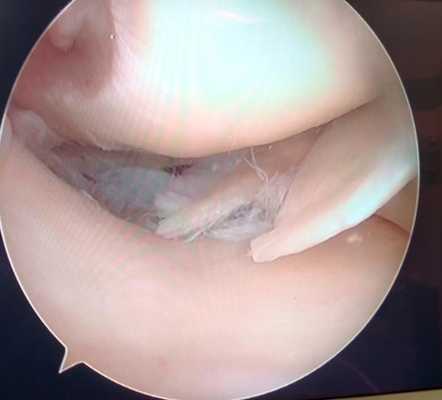

Разрыв внутреннего мениска по типу «ручки лейки» с блоком коленного сустава (невозможность полностью разогнуть коленный сустав). На фотографии хорошо виден крупный фрагмент мениска плотно зажатый между суставными поверхностями бедренной и большеберцовой кости.

Дегенеративный комбинированный разрыв тела и заднего рога внутреннего мениска коленного сустава.

Продольный разрыв заднего рога наружного мениска, сопровождающийся его гипермобильностью. При таком разрыве мениск может значительно смещаться внутрь сустава создавая ощущение механического блока, инородного тела, нестабильности в суставе, заклинивания, щелчков.